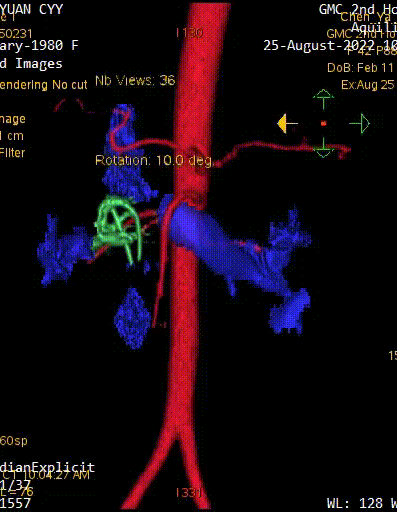

图为:入院CT及增强

图为:CT 三维重建